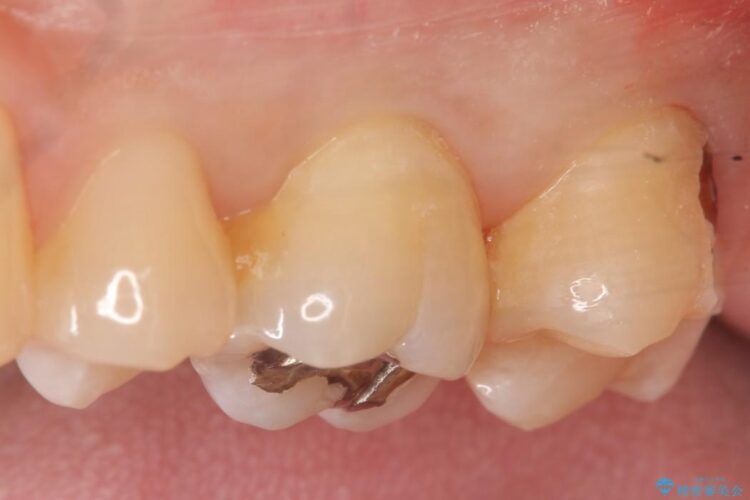

上顎左の一番奥の歯が深い虫歯になって脆くなり、更にその状態に強く噛みしめたわけではない通常の咬合力が加わったことで歯が欠けてしまっていました。

今回は一番奥の歯という位置と、噛み合わせ、清掃状態を加味して適合の高く長持ちするゴールドインレーにて治療することとしました。